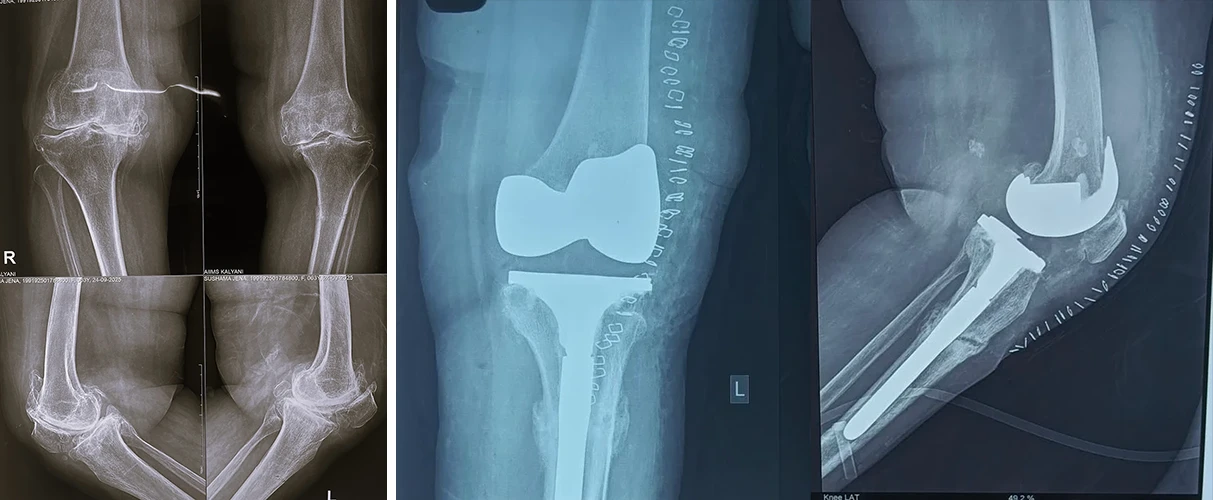

Total Hip & Knee Arthroplasty

During his two year Post Doctoral Programme , he attained rigorous & specialised training in Arthroplasty, focusing on Primary, Complex Primary, Revision & Robotic Total Hip and Knee replacement.

Total Knee Replacement

Are you having pain in your knees? Look no further, because Dr. Sanyal is the best choice for you. He specialises in total knee replacement surgery, offering you a solution to regain your mobility and live pain-free.